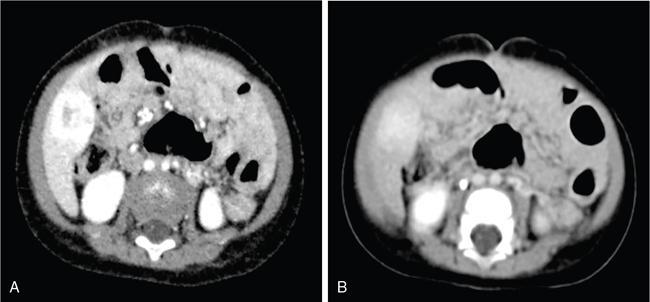

DIFFUSE PARENCHYMAL DISEASES OF THE LIVER Ishan Kumar, Ashish Verma The hepatic parenchyma is the site for multiple essential, interrelated, and complex metabolic activities to assimilate nutrients, detoxify the body, and synthesize vital molecules such as enzymes, hormones, cofactors and essential components of the coagulation pathway. The chemical reactions involved in each of these activities pose a threat to the hepatocytes, which may be damaged leading to the initiation of reparative processes. Further, the liver, being a highly vascular organ with multiple metabolic activities, is liable to be involved in many systemic vascular and metabolic disorders. On one hand, such changes cause healing of the tissue injury, but on the other hand, lead to diffuse parenchymal changes, which may result in suboptimal functioning of the organ. Such a condition is labelled as ‘diffuse liver disease’ and includes (a) diseases caused due to storage of certain chemical products of such chemical reactions labelled as ‘storage disorders’, (b) diseases caused due to reduction of blood flow to the organ, (c) parenchymal injury due to stasis of bile at various levels in the pathway due to varied causes, and (d) involvement of liver in systemic or organ-based inflammatory disorders. The mainstay of diagnosis of diffuse liver diseases is the detection of alterations in the biochemical parameters in blood indicative of liver function, which however is nonspecific to various aetiologies. The diffuse liver diseases in children are quite different from those in the adult population and constitute mainly of congenital or inherited metabolic and vascular diseases as opposed to diseases of acquired aetiologies in the latter population. The gross and microscopic pathological changes are accordingly different in the paediatric population and may be utilized to add specificity to the biochemical indicators as far as aetiological diagnosis is concerned. The invasive and potentially hazardous sampling mandated for histological evaluation of liver parenchyma has been replaced by an array of imaging modalities in recent times. The present chapter presents a review of the currently available imaging modalities (viz. cross-sectional imaging modalities such as ultrasonography, computed tomography [CT] and magnetic resonance [MR] imaging) for evaluation of diffuse liver diseases along with the pertinent imaging features and guidelines for their rational use in various indications. Also a short review of certain key technical and technological details is included. Jaundice and hepatomegaly are the most common clinical manifestations of liver disease. Anorexia is a nonspecific sign, often present in acute or chronic liver disease. Jaundice is a sign of increased bilirubin content in the blood, that can exist in four forms: (i) unconjugated bilirubin bound to albumin, (ii) unbound unconjugated bilirubin, (iii) conjugated bilirubin and (iv) δ fraction. Direct fraction includes both conjugated bilirubin and δ bilirubin. Conjugated hyperbilirubinemia is due to decreased excretion by liver or biliary tract obstruction. Pruritus, spider angioma on face and neck, ascites, portal hypertension, botchy palmer erythema, subcutaneous xanthoma, gastrointestinal (GI) variceal bleed, encephalopathy, renal dysfunction and pulmonary involvement are manifestations of advanced cirrhosis. Evaluation of total serum bilirubin and its fractional analysis into indirect (unconjugated) and direct (conjugated and δ fraction) bilirubin helps to distinguish between elevation caused by haemolysis and that due to hepatic dysfunction or biliary obstruction. Elevations in alkaline phosphatase (ALP), 5′ nucleotidase, and γ-glutamyl transpeptidase (GGT) levels are an indicator of biliary obstruction. However, it should be noted that normal growing children have significant elevations of serum ALP activity. AST (aspartate aminotransferase) and ALT (alanine aminotransferase) are significantly raised in acute hepatitis. ALT rise disproportionate to AST rise is seen in viral hepatitis. A predominant rise in AST is seen in echovirus infection, various metabolic diseases or alcohol-induced hepatitis. These aminotransferases are also elevated in NAFLD/NASH. ALT/AST rise is less marked in chronic liver disease. PT-INR, serum albumin levels can evaluate the hepatic synthesis function. Hypoalbuminemia suggests a bad prognosis. γ-Globulin is elevated in autoimmune hepatitis (AIH). Alpha-fetoprotein is raised in hereditary tyrosinemia or hepatic neoplasms. Indications of liver biopsy in the paediatric age group include neonatal cholestasis, metabolic liver disease, NAFLD, congenital hepatic fibrosis, abnormal biochemical liver tests of unknown aetiology, intestinal failure associated liver disease, acute liver failure and liver tumours. Although biopsy of children and infants is considered a safe procedure, due to incidences of shock, the North American Society for Pediatric Gastroenterology and Nutrition (NASPGHAN) has recommended liver biopsy in children not to be necessarily performed as outpatient procedures. Sonography-guided percutaneous liver biopsy has been reported to be safer, more efficient, more comfortable and only marginally more expensive than blind biopsy. The use of coaxial technique, determination of the number of passes and use of track embolization were at the discretion of the interventional radiologists. In cases of uncorrected PT-INR elevation, transjugular liver biopsy can be performed. Ultrasound (US) is a valuable tool in the diagnosis and management of diffuse liver diseases. It provides useful information about the size, surface, parenchymal architecture, biliary channels and blood flow of the liver. US examination of the liver is performed in the supine position with a convex (5–7.5 MHz) probe. High-frequency (7.5–12 MHz) linear transducers can be used in young infants because of their small size. US examination can be completed with the colour Doppler technique and US elastography, if needed. CT protocol typically requires image acquisition during the multiple phases with a slice thickness of 5 mm or less and a pitch ranging from 1 to 1.5. Contrast injected is 2 mL/kg through manual or mechanical injection. The arterial phase begins at 10–15 seconds and the portal phase is at 20–40 seconds after contrast injection. Equilibrium phase is obtained at 3 minutes, when needed. MRI protocol to evaluate paediatric liver chiefly includes free-breathing sequences, due to the challenge offered by an inadequate breath-hold in these patients. Due to the same reason, motion insensitive single-shot HASTE sequences or motion insensitive T1-weighted spoiled GRE single-shot sequences are also widely utilized in paediatric MR examinations. In slightly older children with a relatively uniform breathing pattern, external trigger signals from a breathing belt, or navigator techniques may be used to overcome motion artefacts from breathing. T1- and T2-weighted turbo spin-echo (TSE) sequences and T2-weighted single-shot sequences in axial and coronal planes are initially acquired to evaluate the anatomy and screen for pathologies. This is followed by a gradient echo (GRE) images to examine vascular structures. Multiecho images with T1-weighting can be acquired to evaluate the fat content of lesions. Contrast-enhanced MRI with intravenous injection of gadolinium (Gd)-based contrast agent is performed as routine in cases with suspected portal hypertension or in any associated suspected neoplastic lesion. This is usually clubbed with MRA for vascular mapping. Arterial phase and portal phase should be acquired 10–15 seconds and 20–30 seconds, respectively after the start of contrast agent injection. GRE T1-weighted sequence should be repeated continuously four or five times to include achieve all phases of liver perfusion. Finally, steady-state imaging should be performed in the equilibrium phase (3 minutes) using T1-weighted and T1-weighted fat-suppressed imaging sequences. MRI contrast media should be administered with caution after evaluation of eGFR, and is safer than the iodinated contrast media needed for CT scan examination, and is hence preferred. Liver size measurement is commonly obtained in one of the two ways (a) an anterior to the posterior measurement of the liver in the midclavicular line, (b) a dome-to-tip longitudinal measurement of the liver in the midclavicular line. Table 9.8.1.1 provides suggested upper limit values of liver and spleen length for various paediatric age groups. Despite advances in 3D US, volume measurements of liver size have not been incorporated in the routine clinical practice because it is time-consuming, requires considerable skill and technically difficult fusion of multiple 3D sweeps. Nonalcoholic fatty liver disease (NAFLD) is referred to as triglyceride accumulation in hepatocytes and encompasses a broad range of clinicopathological entities ranging from simple steatosis, steatohepatitis to cirrhosis. Its worldwide reported prevalence is approximately 2.6%–10% in the general paediatric population and as high as 38% of obese children under the age of 19 years. In India, the reported prevalence is as high as up to 22% in the general paediatric population and up to 45% in obese and overweight children. Hepatic steatosis currently is the most common cause of chronic liver disease in paediatric patients. Table 9.8.1.2 highlights the causes of hepatic steatosis in paediatric age group. The pattern of injury is similar to alcoholic liver disease. Nonalcoholic steatohepatitis (NASH) constitutes a subset of NAFLD, ranging from simple steatosis to inflammation and fibrosis. NASH in children has two distinct histological subtypes. Type 1 NASH resembles adult subtype with macrovesicular steatosis, lobular inflammation, and ballooning degeneration and perisinusoidal fibrosis. Type 2 NASH shows steatosis with portal fibrosis and is present in younger children with increased severity of obesity. ALT can be normal in 20% of the patient with NAFLD and liver biopsy is the gold standard for diagnosis as well as a semiquantitative assessment of disease severity. In clinical practice, the diagnosis and monitoring of NAFLD largely rely on ultrasonography. Grade I fatty liver refers to diffusely hyperechoic parenchyma with a well-visualized diaphragm (Fig 9.8.1). Bright liver with loss of periportal echogenicity and indistinctly visualized vessels is referred to as grade II and blurring of the diaphragm is classified as grade III fatty liver. Limitations of the US are lack of objective quantification and diminished sensitivity in cases where biopsy-proven steatosis ratio is less than 30%. Moreover, hepatic fibrosis and inflammation in cases of NASH are sonographically indistinguishable from simple steatosis. Contrast-enhanced US can diagnose the presence of fibrosis in NAFLD, which is evident from the decreased accumulation of microbubbles in the liver parenchyma. The distinction between hepatic steatosis and fibrosis is important clinically, as fibrosis can progress to cirrhosis if left untreated. US elastography has emerged as a promising technique to screen the children with NAFLD to look for ongoing steatohepatitis/fibrosis. Transient elastography is the most popular elastography technique which has shown excellent accuracy in the adult population with chronic hepatitis. However, its accuracy in NAFLD is significantly lower and the data of effectiveness in the paediatric population is limited. Acoustic radiation force impulse imaging (ARFI) has been shown to have a good correlation with AST/ALT ratios in obese children with NAFLD. An ARFI elastography value of >1.19 m/s predicts NASH-related hepatic changes in these patients while a value >1.75 m/s is suggestive of cirrhosis. Another study on shear-wave elastography has shown a high correlation in paediatric NAFLD patients with biopsy-proven hepatic fibrosis. A value of >5.1 kPa strongly predicts the presence of fibrosis whereas a value of >6.7 kPa is suggestive of stage ≥F2 fibrosis (Brunt scoring system). CT is a common modality utilized for assessment of hepatic pathologies, however is seldom used for assessment of NAFLD because of the risk of ionizing radiation. On noncontrast CT, liver attenuation <40 HU or hepatic attenuation 10 HU lesser than that of the spleen is considered as a sign of steatosis. Recent literature advocates the utilization of MRI in the evaluation of NAFLD. Fat imparts high signal intensity to the liver parenchyma on T1-weighted spin-echo MR images while it is mildly hyper- to hypointense on T2-weighted images. Conventional spin-echo imaging is relatively insensitive to mild-to-moderate fatty infiltration of the liver. The most commonly employed technique for detection of steatosis is chemical shift imaging (Dixon technique or dual-echo method) which utilizes two sets of gradient-echo images of the liver, that is in-phase and out-of-phase. On in-phase echo-time, water and fat signals add whereas, on out-of-phase echo-time, water and fat signals cancel each other. In nonfatty livers, the signal intensity of the liver parenchyma is unchanged between in- and opposed-phase images whereas a fatty liver shows a notable reduction of signal intensity on the opposed-phase images. Iron deposition in the liver can interfere with the assessment of steatosis. MR spectroscopy has been one of the most reliable techniques for the evaluation of hepatic steatosis (Fig 9.8.1.2). Protons in water molecules resonate at 4.7 ppm while that in triglyceride molecules resonate predominantly at 1.3 ppm. Other smaller lipid peaks can be obtained at 0.9, 2.0, 2.2 and 5.3 ppm. In a healthy nonfatty liver no triglyceride peak should be present. The presence of fat can allow measurement of area under water peak versus area under fat peaks to procure hepatic fat fraction. Proton density fat fraction (PDFF) measurement by MRI is another promising objective technique for quantification of steatosis in the paediatric patient. PDFF is the ratio of the density of mobile fat protons and the total density of protons including that from triglycerides and mobile water. Magnetic resonance elastography (MRE) is suggested as a noninvasive tool to evaluate liver stiffness that correlates with the degree of fibrosis. The technique is based on measuring the propagation of shear waves through liver parenchyma. A cut-off value for liver stiffness of 2.27 kPa has been suggested to predict Ludwig grade 2 or higher fibrosis. The technique depends on measuring the propagation of shear waves through the hepatic parenchymal fibrosis and differentiation of low-grade fibrosis from high-grade and also it may be feasible to distinguish steatosis from steatohepatitis. Success rate and accuracy of MRE is higher than US-based transient elastography. Cirrhosis is referred to as diffuse end-stage chronic liver disease characterized histologically by fibrosis and nodular regeneration, along with the disorganization of liver architecture. Although various underlying aetiology can lead to cirrhosis in children (Table 9.8.1.3), the most common causes in India are posthepatitic cirrhosis, Wilson’s disease (WD), AIH, biliary cirrhosis, biliary atresia and other metabolic diseases. In 5%–15% cases, the cause of cirrhosis may remain undetermined and is known as cryptogenic cirrhosis. Imaging is central to the diagnosis and management of children with cirrhosis (Fig 9.8.1.3). The role of imaging extends from diagnosis of cirrhosis to identification of complications and detection and characterization of nodules in cirrhotic liver. The imaging findings consist of changes in liver morphology, parenchyma and contour of the liver, vascular changes including portal hypertension, liver nodules and other complications of cirrhosis. Cirrhosis can lead to volume redistribution, which can be evaluated using either the US, CT, or MRI. Signs of early cirrhosis are atrophy of the segment IV, evident on imaging by increased fat segment IV and portal vein and between segment IV and left lobe. Signs of advanced cirrhosis are atrophy of the right lobe and segment IV with compensatory hypertrophy of left lobe and caudate lobe and fatty expansion of GB fossa. In some patients, a sharp notch is seen in the posterior surface of the liver (segment VI/VII). Some aetiology of cirrhosis may have different patterns of volume redistribution such as atrophy of left lobe and posterior segments in primary sclerosing cholangitis, diffuse hypertrophy in primary biliary cirrhosis, and absence of caudate hypertrophy in WD. The US can detect changes in liver segmental volumes based on linear measurements. C/RL (caudate/right lobe) ratio >0.65 calculated by comparing the transverse length of caudate and right lobe at the portal bifurcation, is a sign of cirrhosis. CT/MRI-based segmental volumetric analysis can reflect the morphological changes more effectively. Liver parenchyma in children appears as isoechoic to hypoechoic compared to the renal cortex in the US. The neonatal liver may reveal a bright echotexture. Hyperechoic parenchyma is seen in the fatty liver or liver fibrosis. Cirrhosis is seen as coarse and heterogeneous parenchyma. The liver surface in normal children appears as a hyperechoic, straight and regular line. The liver surface with diffuse irregularity or nodular surface is present in cirrhosis. CT and MRI in frank cirrhosis can reveal heterogeneous parenchyma along with the irregular surface. Diagnosis of early cirrhosis and fibrosis cannot be reliably made by the US where parenchyma may appear within normal limits. Similarly, CT and conventional MR sequences are also insensitive in early cirrhosis although early fibrosis can be seen as T1 hypointense/T2 hyperintense areas on MR and may show subtle enhancement. These T2 hyperintensities can be present as perilobular bands, perivascular cuffing, bands surrounding regenerative nodules, patchy fibrotic areas, or diffuse reticulation (honeycomb pattern). The role of US elastography and MR elastography is increasing in paediatric liver diseases for the detection of fibrosis and early cirrhosis and has been discussed in the previous section. US examination should be complimented with Doppler of the portal vein and hepatic veins if US features are suspicious of cirrhotic or fibrotic changes. The diameter of the portal vein increases with age. The mean diameter of the portal vein is 3.5 mm in children <5 years, 6.3 mm in 6–12-year old children, and 7–11 mm in >12-year-old children. Portal vein diameter is increased in portal hypertension; however, no reliable age-dependent cut-off values exist for the PV diameter in the diagnosis of portal hypertension in paediatric patients. Peak portal vein velocity in the paediatric age group is usually above 20 cm/s in a nonfasting child (15 cm/s in term neonate) along with some respiratory undulation. Peak portal vein velocity <16 cm/s in the paediatric age group is suggestive of portal hypertension. In term neonates, the values are above 15 cm/s. An increase in pulsatility of the portal vein (PI < 0.5) suggests portal hypertension. Reversal of portal vein flow (hepatofugal flow), presence of periportal collaterals or portal cavernoma, umbilical vein recanalization and various other collaterals are other signs of portal hypertension. Hepatic veins should be evaluated to rule out Budd–Chiari syndrome. CT or MR portal venography can comprehensively assess the extent and anatomical location of portosystemic collateral vessels in children with liver cirrhosis. Four groups of collateral channels can be identified: (a) periportal collaterals and portal cavernoma, (b) collaterals draining into SVC, that is left gastric vein (coronary vein), short gastric vein, oesophageal and paraoesophageal collaterals, (c) collaterals draining into IVC such as paraumbilical vein and abdominal wall collaterals, splenorenal and gastrorenal collateral, (d) mesenteric, retroperitoneal and haemorrhoidal collaterals. Various nodules can be seen in the cirrhotic liver including regenerative nodules, dysplastic nodules and HCC. The US is not sensitive in identifying these nodules and high-frequency linear-array transducer can contribute to their detection. CT and preferably MR can be used to characterize these nodules. Table 9.8.1.4 summarizes the imaging findings of these nodules on CT and MRI. It should be noted that HCC is rare in young children although it has been reported in children younger than 5 years in progressive familial intrahepatic cholestasis (PFIC) and Byler disease, biliary atresia. Recognizing the need for paediatric-specific guidelines for standardized interpretation and reporting CT and MR, ACR – LI-RADS (Liver Imaging Reporting and Data System) committee has convened the Pediatric LI-RADS Working Group in 2017. Hepatorenal fibrocystic diseases (HRFCDs) are developmental abnormalities of the liver and portobiliary system with associated fibrocystic degeneration of the kidneys. HRFCDs belong to the larger group of disorders collectively referred to as ‘ciliopathies’ a term describing the group of disorders affecting primary cilia which are an organelle present within the cholangiocytes. The ciliopathies in the liver is manifested as ductal plate malformation. Ductal plate is the embryonic precursor of the intrahepatic bile ducts and their abnormal development leads to cyst formation and alteration in portal venous development. Two major disorders are included in these malformations: (i) congenital hepatic fibrosis (affecting small intrahepatic ducts) and (ii) Caroli’s disease (affecting larger ducts). A combination of the CHF and CD is known as Caroli’s syndrome. Liver function test results in DPM may remain normal or be only modestly elevated. Few of congenital cystic liver pathologies are not associated with ciliopathies, such as autosomal-dominant polycystic liver disease (ADPLD) and portal fibrosis associated with congenital disorder of glycosylation (CDG) type Ib. Tables 9.8.1.5 and 9.8.1.6 innumerate the renal diseases and syndromes associated with ciliopathies. Carbohydrate-deficient glycoprotein syndrome type 1b Renal–hepatic–pancreatic dysplasia Oral–facial–digital syndrome type I US is the first-line modality, which can detect the distinctive morphological features of CHF that includes left lobe (segments II and III) hypertrophy, normal or hypertrophies segment IV, and atrophied right lobe. Preservation of the volume of the left medial segment is a feature that distinguishes CHF from cirrhosis resulting from viral hepatitis. The US can also detect changes in parenchymal echotexture, presence of splenomegaly, and can identify the evidence of cystic disease in the kidneys. Portal hypertension is one of the common presenting features of CHF despite normal hepatic lobular architecture and normal hepatic function. Application of the Doppler technique can detect the features of portal hypertension and cavernomatous transformation of the portal vein which can be present in up to 50% of the cases of DPM. The portal vein shows abnormalities in its ramification pattern with numerous, hypoplastic branches which are closely spaced, referred to as ‘pollard willow’ pattern. Studies have also shown enlarged hepatic artery and regenerative nodules in the arterialized hepatic parenchyma. In cases of Caroli’s syndrome, the US can easily identify cystic lesions or dilated intrahepatic bile ducts and can detect the stones in the ducts. Intraductal bridging (echogenic septa) can be seen traversing the dilated biliary duct lumen. Occasionally, the US can identify small portal venous branches surrounded by dilated biliary duct. Because of the absence of risks of ionizing radiation, US is the modality of choice in these children for long-term follow-up. CT can comprehensively demonstrate the morphological changes of CHF. Segmental computer-aided volumetric analysis of the hepatic parenchyma can identify the volume distribution with higher accuracy compared to the US. CT can also detect the parenchymal changes with higher sensitivity than the US. CT in these patients shows heterogeneously enhancing liver parenchyma, volume changes, and complete vascular mapping of the abdomen in cases of portal hypertension, identifying the portosystemic collaterals. Periportal cuffing can be identified on CT, indicative of periportal fibrosis. In Caroli’s disease, CT shows segmental and noncontinuous, saccular or fusiform dilatation of intrahepatic biliary radicals with the central enhancing dot representing portal vein branches (Fig 9.8.1.4). CT can identify the communication of the cyst with IHBD, differentiating them from PCLD. CT can also better detect the complications of CD such as cholangitis abscesses and cholangiocarcinoma. Seven per cent of the patients of CD can develop cholangiocarcinoma. MRI and MRCP seem to be a sensitive method for revealing biliary and renal abnormalities associated with congenital hepatic fibrosis and CD, even when sonography findings are normal (Fig 9.8.1.5). The parenchymal changes and heterogeneous architecture along with periportal fibrosis can be demonstrated on T2-weighted images, revealing hyperintensity along the portal vein and its branches. Regenerative nodules can be identified on T2-weighted and contrast-enhanced MRI. MRCP can delineate the communication between the cystic lesions and the biliary tree in cases of CD. Contrast-enhanced MRI can aid in the detection of complicating malignancies which can have a wide range of radiological appearances such as focal hepatic mass, intraductal mass, or biliary stricture. Multiplanar capability of MRI can enable its utility for preoperative planning in the affected children obviating the need for invasive preoperative cholangiogram to demonstrate the anatomy of the biliary tree. The differential diagnosis of Caroli’s disease is ADPLD, Von Meyerberg complex, choledochal cyst, sclerosing cholangitis, recurrent pyogenic cholangitis and peribiliary cysts. PCLD is seen on imaging as more than 20 round and smooth cysts without any communication with the biliary tree. Biliary hamartoma (Von Meyerberg complex) are seen as multiple/unique round uniform small cysts measuring 1–3 mm located close to portal tracts. Recurrent pyogenic cholangitis presenting with intra- and extrahepatic biliary dilatation is the most difficult diagnosis to exclude on imaging, however, the presence of saccular dilatation favours the diagnosis of Caroli’s disease. It should be noted that up to 20% of the cases of Caroli’s disease may have associated extrahepatic bile duct dilatation mimicking choledochal cyst and Caroli’s disease may even coexist with choledochal cyst. The presence of diffuse fusiform dilatation of the extrahepatic duct with less than 3 cm diameter combined with the characteristic intrahepatic ductal findings may help differentiate patients with Caroli’s disease from patients with a choledochal cyst associated with intrahepatic biliary dilatation. Routinely 1–2 mg of iron is absorbed by the intestine in a healthy child. Iron is recycled by extravascular haemolysis in the liver to meet the required amount (25 mg) in the spleen and bone marrow through Kupffer cells. Excess iron is bound to ferritin and hemosiderin in the hepatocytes. Excess iron in the body may be deposited in the liver, spleen, lymph nodes, pancreas, kidneys, pituitary, myocardium and GI tract. Up to 10–20 mg of excess iron does not cause tissue damage, in which case the term haemosiderosis is applied. Functional and structural impairment of the tissues occurs if the iron load (50–60 g) exceeds the compensatory mechanisms. In these cases, the term hemochromatosis is applied. Primary hemochromatosis is a genetic disorder occurring through mutation in the HPE gene which causes increased absorption of iron through the intestine. The secondary nongenetic form is more common and is caused due to multiple blood transfusions (transfusional haemosiderosis) in haematological disorders such as myelodysplastic syndrome, aplastic anaemia, beta-thalassemia major (transfusion haemosiderosis). Prolonged and excessive iron deposition can lead to endocrine abnormality, cardiac failure and liver parenchymal disease. Liver biopsy was considered as a reference standard for the detection and quantification of iron overload in hepatic parenchyma. However, it is largely replaced by radiological techniques because of the invasive nature and small size of sampled tissue while doing a single-site biopsy. The US cannot detect the features of iron overload in the liver parenchyma; however, it can be useful in detecting the complications of iron overload such as cirrhosis, hepatocellular carcinoma (HCC) or features of portal hypertension. CT scan is also of limited utility in hemochromatosis. Attenuation of >65 HU (15–130) with low attenuation of hepatic vessels relative to liver parenchyma on noncontrast CT is suggestive of iron overload, however can also be seen in WD, glycogen storage disorder, long-term amiodarone administration. MRI is the primary radiological modality used for diagnosis of iron distribution, quantification and monitoring of treatment response in liver iron overload (Fig 9.8.1.6). Various MRI techniques have been devised for iron overload estimation. This technique compares the signal intensity of liver parenchyma with the signal intensity of paraspinal muscles, which are assumed to be unaffected by iron content. GRE sequences are obtained with TR of 120 ms, flip angle 200, and varying TE of 2, 4, 9, 14 and 20 ms. Three ROIs of 1–2 cm are drawn in liver parenchyma and one on each paraspinal muscles. Liver iron concentration can then be obtained using a free online calculator provided by the University of Renne. Images are obtained with TR 2500 ms, flip angle 900 and variable TE of 6, 9, 12, 15, 18 ms. The images can be used to draw automated ROI covering the right lobe of the liver (excluding vessels) in the largest area and a T2 map of the same images can be generated. The technique quantifies the T2 shortening due to proton exchange between bulk water and exchangeable protons in ferritin. T2* takes into account the contributions of the T2 (1/R2) effects and the microscopic inhomogeneities introduced in (B0) by the hemosiderin clusters. For T2* measurement single breath-hold multiecho GRE sequences with TR of 25 ms, flip angle of 20 degrees, TEs every 0.25 ms from 0.8 to 4.8 ms are obtained. R2 * (1/T2*) values can be generated with ROI drawn from a single midhepatic section by drawing an ROI following the boundaries of the liver and excluding hilar vessels. Liver iron concentration can be obtained using a formula: [Fe] = 0.202 + 0.0254 R2*. This technique detects the enhancement in the local magnetic field caused due to ferritin or hemosiderin using a 3D breath-hold multiecho GRE sequence with the use of chemical shift–encoded water/fat separation, T2*/R2* mapping, and B0 field mapping. A quantitative susceptibility map of the parenchyma is generated. A local relative susceptibility value (ΔB0) is obtained drawing ROI which is expressed in parts per million (ppm), related to local iron deposition. With the ongoing research, stress is being placed upon the multiparametric quantitative MR imaging protocol which includes MR elastography (for fibrosis), multiecho chemical shift–encoded GRE to measure proton-density fat fraction (for steatosis quantification) and R2* relaxometry (for iron overload estimation). Hepatic iron overload has been shown to predispose to the development of HCC in the younger age group. The detection of HCC in the setting of iron overload is less difficult on T2-weighted sequences because the presence of iron behaves like a nonspecific contrast medium, such as superparamagnetic iron oxide (SPIO). However, care should be taken while evaluating these lesions, which may appear like hepatic cyst or haemangioma. Any nodule detected in these patients should be evaluated and characterized by the use of intravenous gadolinium contrast. The liver processes various metabolic processes of the body and hence it can be affected by multiple inherited metabolic disorders. The affection of the liver in these disorders may be in the form of hepatomegaly, cholestasis, acute liver failure or hepatic encephalopathy. WD is an autosomal recessive disorder of copper metabolism, first described in 1912 by Samuel Kinnier Wilson. The primary defect is a genetic abnormality located at chromosome 13 and q14.3, coding for copper-transporting P-type ATPase. An average diet contains 3–5 mg copper, 40% of which is absorbed in the upper GI tract and which is almost completely excreted in bile. The genetic defect leads to abnormality in this excretory function that leads to copper accumulation in the liver and other organs and tissues including brain and cornea. Liver disease in WD can range from asymptomatic transaminasemia, acute or chronic hepatitis, fulminant hepatic failure, and cirrhosis. WD can be misdiagnosed as AIH because both can result in similar autoantibodies. Imaging findings of liver manifestations can be categorized into four groups: (i) morphological changes, (ii) parenchymal changes, (iii) perihepatic changes, (iii) other findings. On CT, copper deposition in the liver may present with increased attenuation of the hepatic parenchyma, however, associated hepatic steatosis can decrease the overall attenuation which is within normal limits in most of the patients. Contrast-enhanced CT can show hypodense as well as hyperdense nodules and surface irregularity. The disappearance of hyperdense nodules has been documented after penicillamine therapy. Various MRI features of liver disease in WD has been described in the literature that includes (a) T1 hyperintense/T2 hypointense nodules (2 mm to 1 cm), (b) T1 hypointense nodules, (c) multiple hyperintense septae leading to ‘honeycomb pattern’, (d) high-intensity septa, (e) absence of parenchymal changes on MR. 31P MR spectroscopy of the liver in WD can show elevated phosphomonoester (PME) resonance and reduced phosphodiester (PDE) resonance, which have been shown to normalize after penicillamine and vitamin K therapy. Gaucher disease (GD) results from a deficiency of lysosomal enzyme β-glucocerebrosidase leading to the accumulation of ‘Gaucher cells’ in various organs. Imaging can help in the detection and characterization of liver infiltration, hepatomegaly, fibrosis, cirrhosis, iron deposition and HCC, all of which are associated with GD. On imaging, hepatosplenomegaly is the hallmark of GD (Fig 9.8.1.7). Recent literature recommends the utilization of CT or MRI over the US for volumetric assessment of liver and spleen sizes in GD with the expression of liver volume as multiples of normal volume (MN). Weight-based formula is used for calculation of liver and spleen volumes: normal liver volume (mL) = 25 × weight (in kg) ; and normal spleen volume (mL) = 2 × weight (in kg). A target liver volume of 1–1.5 MN and a spleen volume of 2–8 is aimed by the therapeutic regimens. On MRI, low ADC of liver and spleen indicates greater infiltration and worse prognosis, with ADC values correlating with chitotriosidase levels. Fibrosis can be detected and quantified using US shear-wave elastography, MR elastography, and nonimaging–based transient elastography. Studies have indicated the presence of liver iron deposition in GD due to associated hyperferritinemia, which can be quantified using R2* relaxometry. Hepatic nodules can be identified on imaging on GD. Most commonly these nodules represent a focal accumulation of Gaucher cells and are known as ‘Gaucheroma’. These lesions are hyperechoic on the US, hypoattenuating on CT, T1 hypointense/T2 heterogeneous nodules on MRI. These lesions do not merit biopsy; however, care should be taken to identify the lesions suspicious for HCC, that is large, irregular, hypoechoic, hypervascular lesions, which mandate further evaluation by multiphasic contrast CT or MRI. Besides the liver, evaluation of abdominal imaging should attempt to detect changes in spleen and visualized bones. GD in the spleen can manifest with splenomegaly, fibrosis, nodules, subcapsular infarcts and splenic necrosis. Osseous features of GD are osteopenia, osteonecrosis, pathological vertebral fractures and Erlenmeyer flask deformity. These are a group of disorders caused by defects in metabolism or storage of glycogen which broadly present with hepatic, myopathic, cardiac or other manifestations. GSD type I (Von Girke disease) presents with hepatic involvement. The US in these patients shows hyperechoic liver parenchyma because of fatty replacement and glycogen deposition. CT shows variable attenuation because hepatic attenuation is increased by glycogen and decreased by steatosis. There is a well-known association with GSD and hepatic tumours such as adenoma, focal nodular hyperplasia and HCC (rare). Adenomas are the most common tumours in GSD which show variable echogenicity. These lesions may contain fat, haemorrhage, or rarely dystrophic calcifications. A fat component can be detected using chemical shift MRI. These lesions should be monitored serially and malignancy should be suspected in case of rapid growth. α1-Antitrypsin deficiency is a rare autosomal recessive disorder that can cause chronic severe paediatric liver disease. In infants, this disorder can have a presentation similar to biliary atresia or idiopathic neonatal hepatitis. Moreover, scintigraphy cannot distinguish between biliary atresia, because similar to atresia, it can show uptake by hepatocytes and absence of biliary excretion due to paucity of lobular biliary ducts. The US in the neonatal period can help distinguish between the two, as it shows normal gallbladder and hepatic parenchyma. Older children may show imaging evidence of hepatic fibrosis or cirrhosis. MR elastography in this disorder is accurate for identifying fibrosis with a cut-off value of >3 kPa predictive of fibrosis. Various systemic illnesses can present with liver disease. The table summarizes the hepatic manifestations of various systemic liver diseases. TABLE 9.8.1.7 Paediatric diffuse liver diseases though forming a small subset of overall morbidity in children pose a formidable challenge for diagnosis as most cases present at a relatively early age. Imaging in these cases aims to make an aetiological diagnosis and rule out any associated complications, as the initial diagnosis is usually established by the biochemical analysis of liver function. Screening sonography usually forms the initial screening modality with MRI being the next stop problem-solving modality. CT scan has taken a back seat in current practice due to radiation exposure and the need to inject iodinated contrast media, both of which can be obviated by MRI. The former modality however remains essential in case an interventional procedure to treat portal hypertension is contemplated or percutaneous sampling from areas difficult to access by sonography is to be done. With the availability of an array of imaging modalities, it remains essential for an imaging expert to be clear as far as the choice of modality and order of its usage during the course on management is involved so that the most optimum imaging protocol can be offered to the patient. PEDIATRIC BENIGN HEPATIC MASSES (INCLUDING INFECTIONS) Kushaljit Singh Sodhi, Anmol Bhatia, Akshay Kumar Saxena Liver neoplasms constitute around 2% of all neoplasms seen in the pediatric population, and around 6% of the total abdominal neoplasms. Only one-third of the liver tumours in children are benign, while two-thirds are malignant. Benign hepatic tumours in children include lesions which are specific to children like mesenchymal hamartomas and vascular tumours, and the lesions that are also seen in adult population, such as adenoma, focal nodular hyperplasia (FNH) and nodular regenerative hyperplasia (NRH). Further, benign hepatic lesions affecting children include a wide variety of infections of bacterial, fungal and parasitic origin. In the present chapter, we will be discussing about the benign hepatic tumours and hepatic infections commonly seen in the pediatric population. A wide variation has been reported in the use of terminology for the hepatic vascular malformations in literature. According to the standard nomenclature adopted by the International Society for the Study of Vascular Anomalies (ISSVA), liver vascular tumours in children are termed as liver hemangioma. Liver hemangiomas in children are classified as infantile and congenital. Infantile hemangiomas usually begin to grow after birth, continue to grow during the first year of life and enter an involuting phase between 1 and 7 years. These tumours are positive for glucose transporter-1 protein (Glut-1), a protein that facilitates the transport of glucose across erythrocyte cell membranes. On the other hand, congenital hemangiomas are fully developed at birth and are characterized by Glut-1 negativity. These are further subdivided into a rapidly involuting group and a noninvoluting group, with some overlap between these groups. Hemangioma is a model of the angiogenesis concept proposed by Folkman et al and its development is related to a combination of upregulation of factors that promote angiogenesis and downregulation of its inhibitors. Most of these tumours are diagnosed in the first year of life, with these being slightly more common in females. Most commonly, these present as an asymptomatic mass in abdomen; however, associated life-threatening presenting complications have also been reported. These include high-output cardiac failure as a result of large arteriovenous shunts or Kasabach–Merritt syndrome of coagulopathy, severe hypothyroidism and acute hemoperitoneum due to tumour rupture. Lesions can be focal, multifocal or diffuse. Multifocal lesions are usually small and homogenous in appearance, while larger lesions may show areas of hemorrhage, calcification, fibrosis and necrosis. The liver is grossly enlarged in diffuse disease, which may cause mass effect on surrounding organs and vessels. Multifocal lesions frequently are associated with multiple cutaneous infantile hemangiomas with a Glut-1 positive marker. Biopsy of these masses should be avoided as there is a risk of bleeding, and the diagnosis is made based on typical imaging features and involution at follow-up. Well-defined hypoechoic or hyperechoic lesion, which may show heterogenous echotexture because of central hemorrhage/necrosis. A variety of flow patterns may be seen on colour Doppler due to the presence of shunts which may be portosystemic, or arteriovenous shunts. The hepatic arteries and veins usually enlarged, with large feeding arteries and draining veins seen surrounding as well as within the lesions. The lesions are usually hypoattenuating to the liver parenchyma with speckled calcifications seen in up to 50% of cases. The enhancement pattern is similar to that of hemangioma in adults and shows intense peripheral nodular enhancement on arterial phase with progressive centripetal filling on venous and delayed phases. Small lesions usually show intense and uniform enhancement (Fig. 9.8.2.1). The lesions show hypointense signal on T1-weighted images (T1WI) and hyperintense signal on T2-weighted images (T2WI). The tumour shows internal vascular flow voids and centripetal enhancement (Fig. 9.8.2.2). Heterogeneous signal may be seen due to presence of hemorrhage, thrombosis and necrosis. Calcifications may be seen in about 16% of cases.